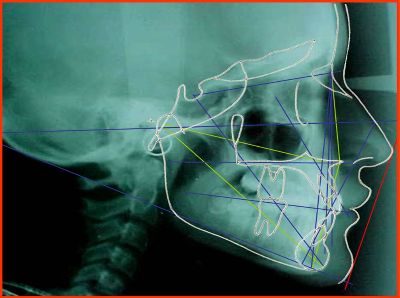

Todas estas alteraciones mencionadas en la cara producen alteraciones de

tipo funcional y estético es por esto que se deben realizar estudios

radiográficos para cada caso, modelos de impresión de los dientes, fotos

faciales y de la mordida con la finalidad de realizar un análisis

detallado de las proporciones faciales, la línea media, la mordida,

realizando montajes en articuladores que nos determinen la mejor posición

de los maxilares para lograr una mejor mordida y a la vez unos cambios más

armónicos de la cara que nos hacen ver mejor. También se incluyen aquellas